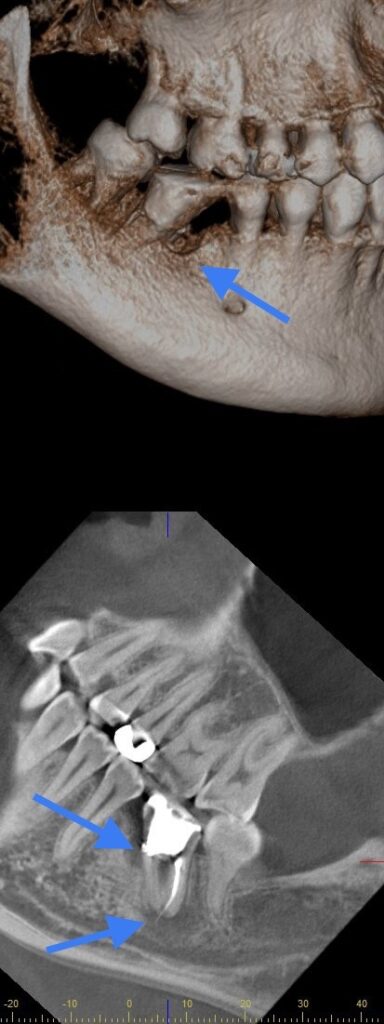

歯科医院には日々、「歯ぐきが腫れた」というお悩みの患者さんがたくさんいらっしゃいます。 多くは歯石がついている事による歯周病が原因です。 しかし、中には他の理由で歯ぐきが腫れている方がいらっしゃいます。 今日はそのうちの一つ、 根管治療後に、根に穴があいている(穿孔している)ことが原因で起こる炎症についてお話しします。 この方は以前、根の治療(いわゆる神経の治療)を受けたが、 歯ぐきが腫れて痛いというお悩みで来院されました。 レントゲンで確認します。 白いところは詰め物です。 根の周囲の骨が、周りよりも一層黒く映っています。 これにより、この部分は炎症で骨が溶けてしまっているということがわかります。 では、なぜ骨は溶けてしまったのでしょう。 最初にお話ししたように、骨が溶ける原因の多くは歯石がついていることによる歯周病です。 しかし今回の場合は、この歯の周りに限局して炎症が進んでいます。 実は、他に原因があるのです。 CTを撮ってみました。 よく見ると、白く映っている詰め物が歯の外側に出ているのがわかります。 そして、その周囲に炎症が広がり、骨が溶けているのです。 別の角度から見てみましょう。 根の先端から歯の横のほうにかけて骨がなくなっています。 また、この炎症の範囲が、 「下歯槽管」という顎骨の深いところを通っている管に近接していることが分かります。 ここには大事な神経や血管が通っており、炎症が波及すれば神経症状が出てくることもあります。 歯の外側に汚染物質が出ていて炎症が広がっている場合、 根の治療で炎症を治すことはできません。 この歯を抜歯して、その周りの感染して悪くなっている部分を取り除く必要があります。 この後、抜歯した時の写真を載せます。 苦手な方は飛ばしてください。 抜歯した穴を見ています。 細菌感染によりブヨブヨになってしまっている部分が見えるので、これを取り除きます。 すると本来の骨が見えてきます。 抜いた歯を見てみましょう。 真ん中のあたりに穴があいているのが分かります。 また、下のほう、根の先端からは詰め物が飛び出しています。 実際にこの周囲で炎症が広がっていました。 抜歯後は、感染している部分を取り除き、治癒を待ちます。 歯ぐきが腫れていた原因の歯がなくなれば、その部分の炎症は数日で落ち着いてきます。 その後、歯がなくなった部分に人工的に歯をまた作り、機能を回復させるのです。 それがいわゆる入れ歯、ブリッジ、インプラントなどです。 いかがでしたか。 ・治療したはずなのに歯ぐきが腫れてきた ・ずっと歯周病の治療をしているけど腫れが治らない というお悩みをお持ちの方は一度アズ歯科桶川院にお越しください。 歯ぐきが腫れている原因は別にあるかもしれません。 治療期間 3ヶ月 治療費 保険治療 治療のリスク 抜歯が必要な可能性が高い